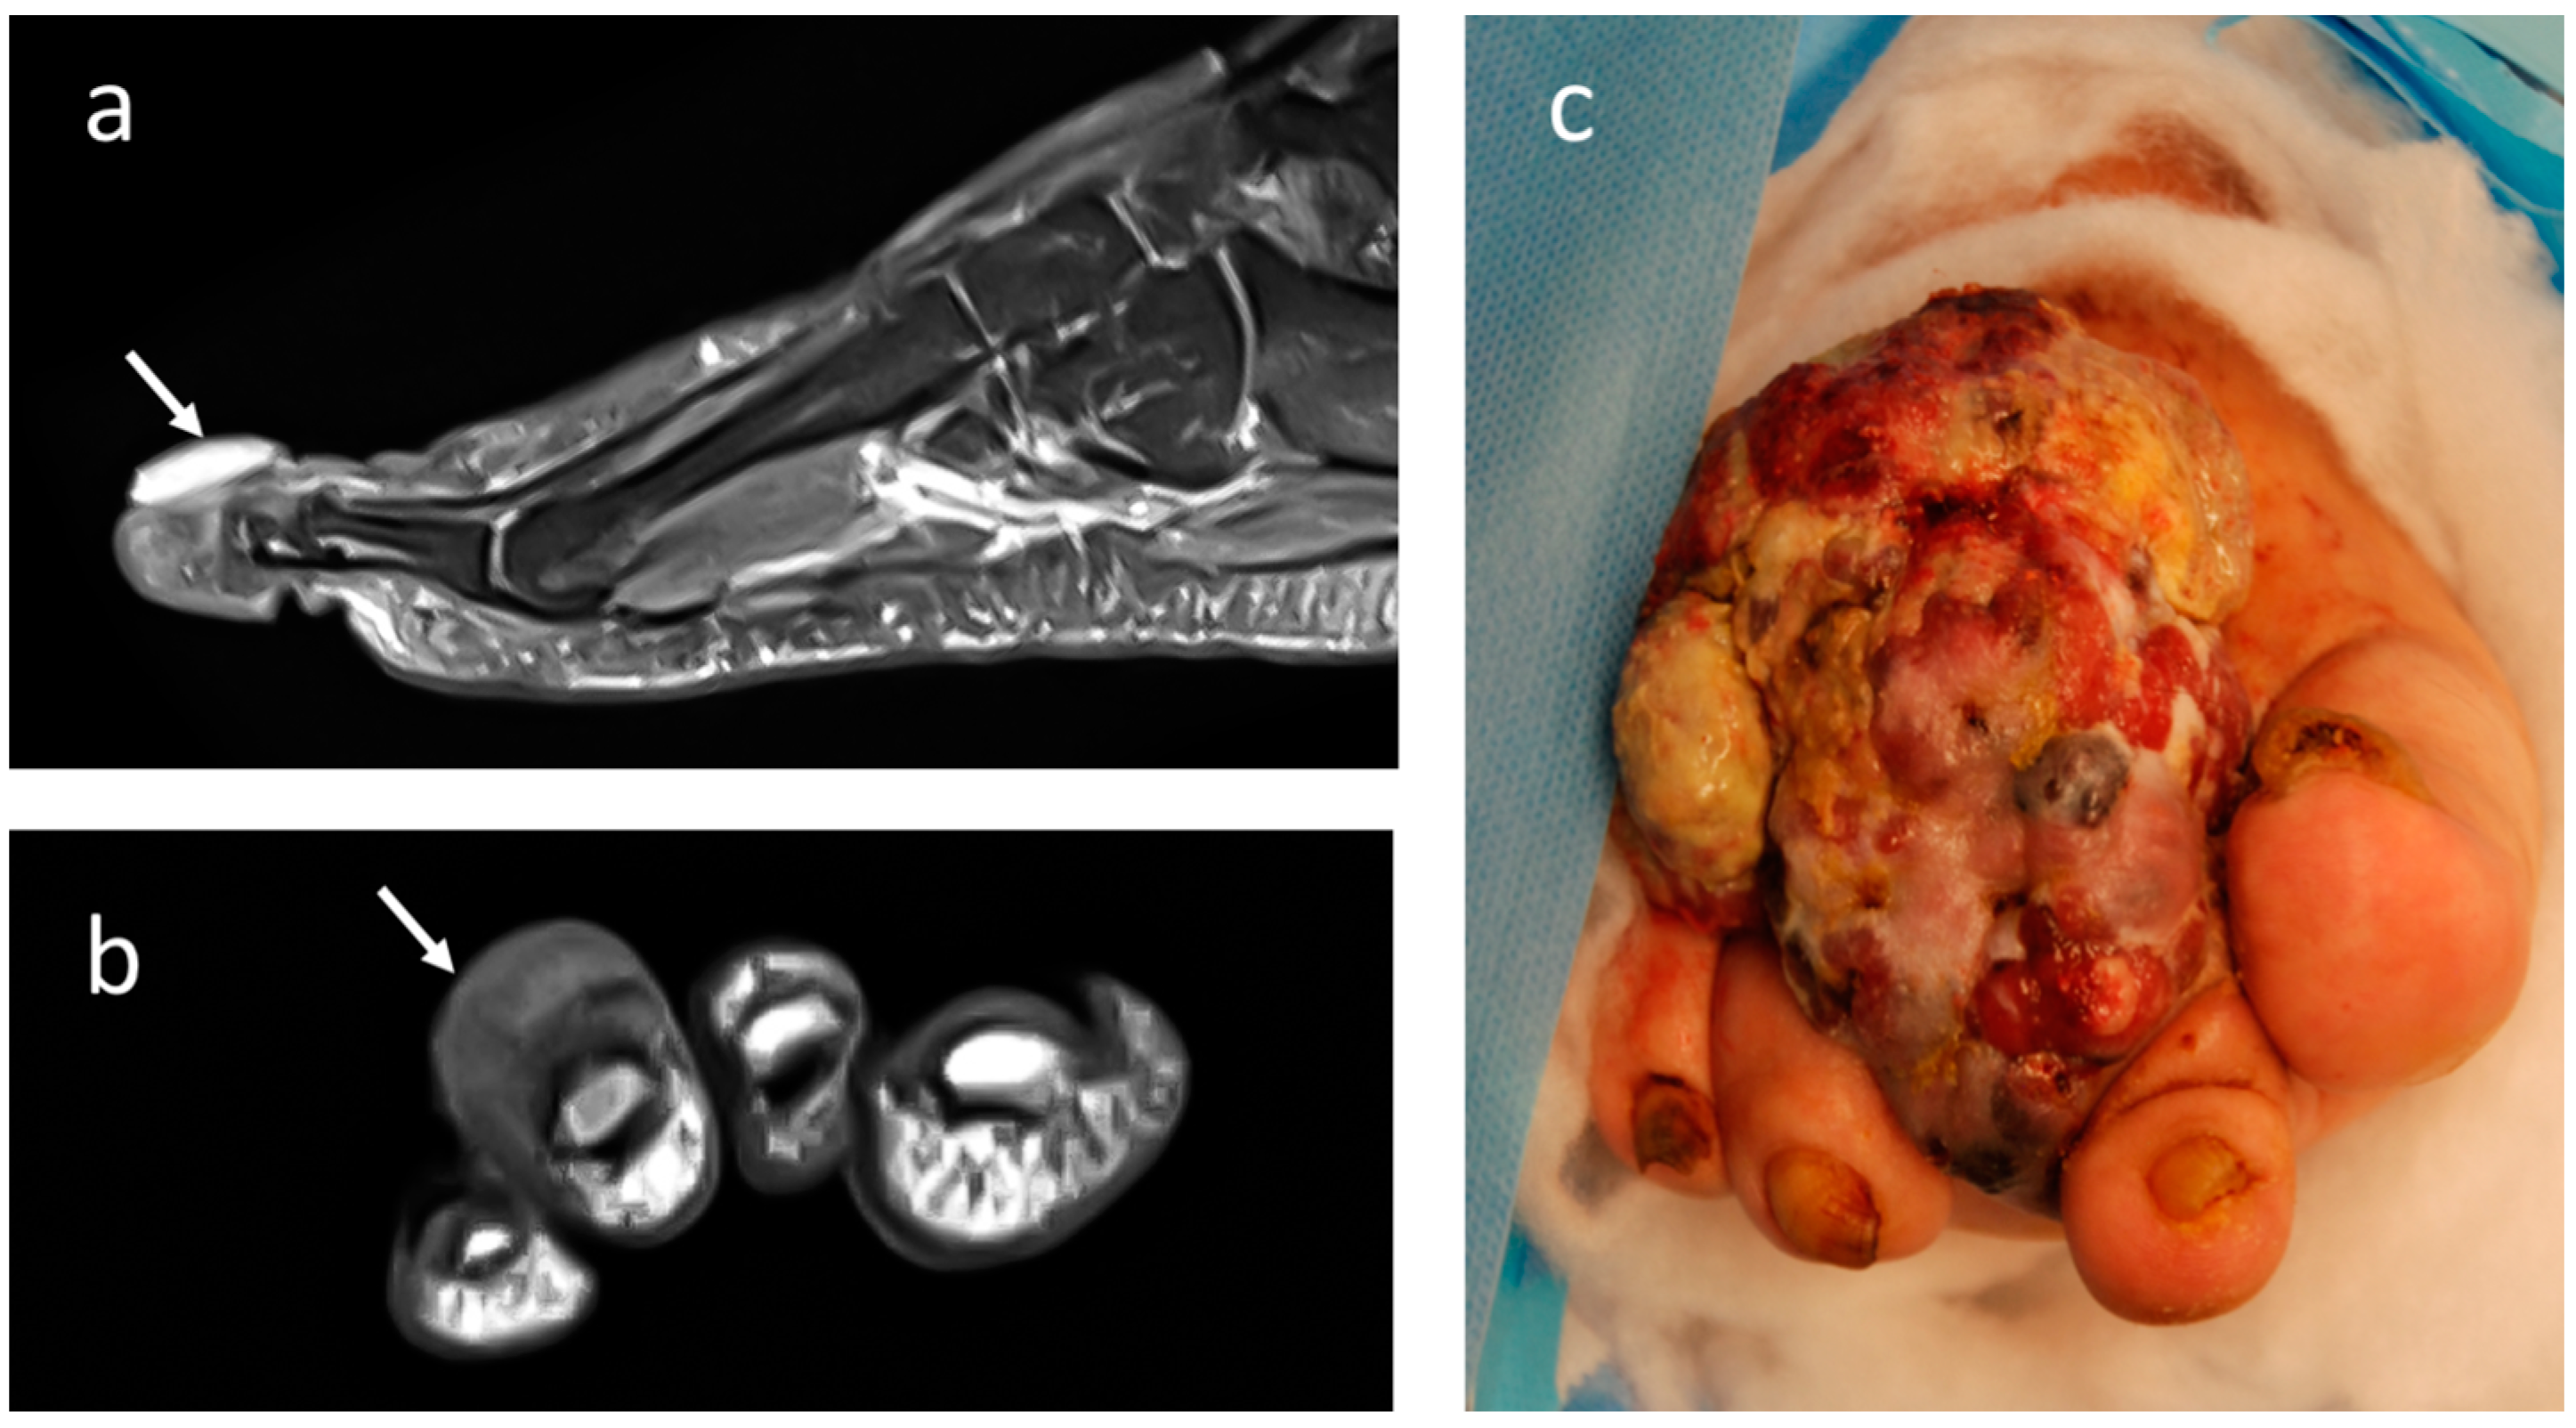

4.1. Melanoma

4.2. Epithelioid Sarcoma

4.3. Synovial Sarcoma

4.4. Clear-Cell Sarcoma